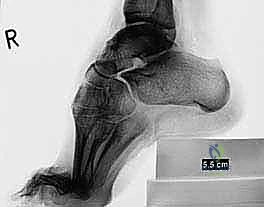

الشكل 2 • تشوهات القدم الجوفاء، منظر أمامي. يوضح مكونات انقلاب الكعب للداخل وتقوس مقدمة القدم، مما يؤدي إلى عدم استقرار الكاحل.

الأشعة السينية العادية (X-rays) أثناء الوقوف (Weight-bearing) هي الأساس. يقوم الدكتور هطيف بقياس زوايا محددة بدقة هندسية:

* زاوية ميري (Meary's Angle): لتقييم مدى تقوس منتصف القدم.

* زاوية ميل الكعب (Calcaneal Pitch Angle): تكون زائدة بشكل كبير في القدم الجوفاء.

* زاوية هيبس (Hibbs Angle): لتقييم التشوه في مقدمة القدم.